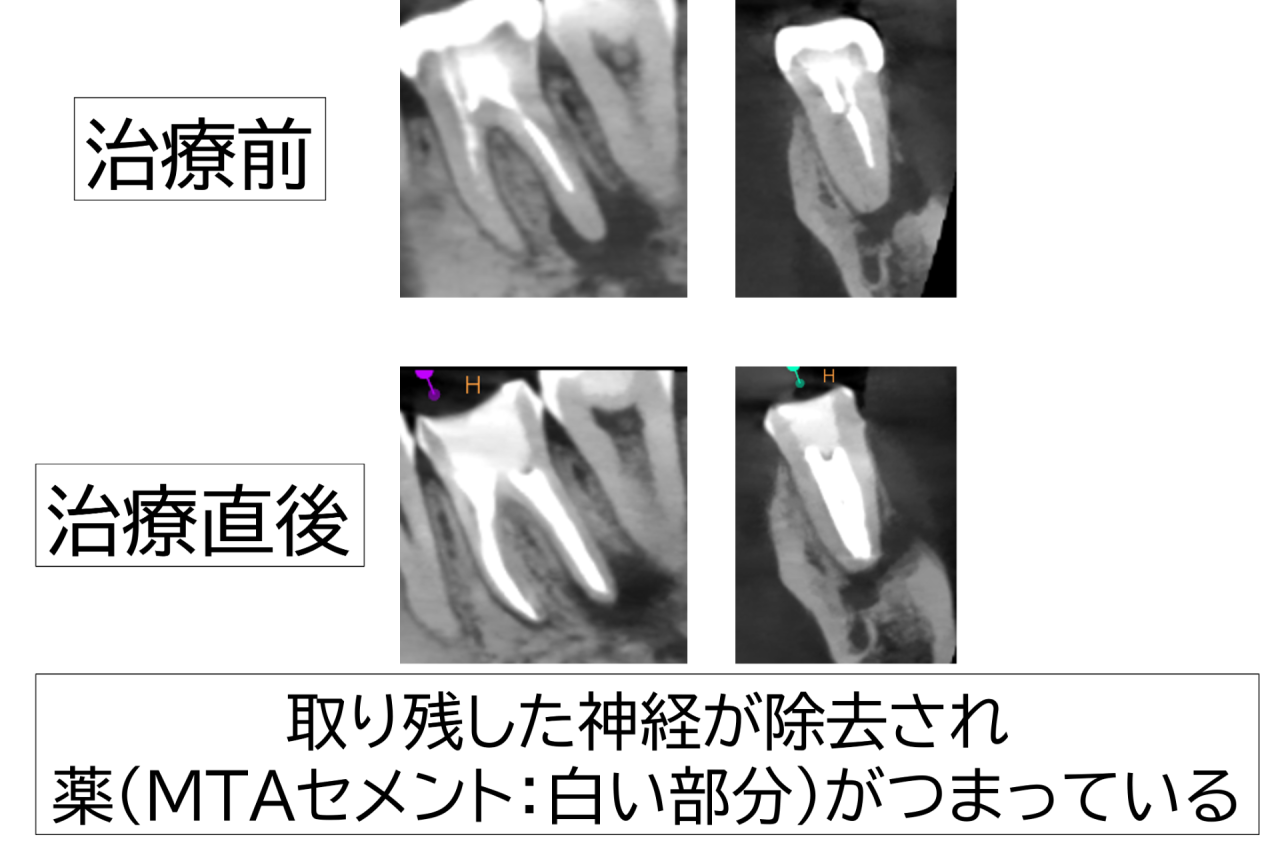

・根管充填

2回目の治療で症状の軽減と排膿の停止、根管内の乾燥が得られたため、すき間ができないように根管を立体的に封鎖しました(MTAセメントを使用)